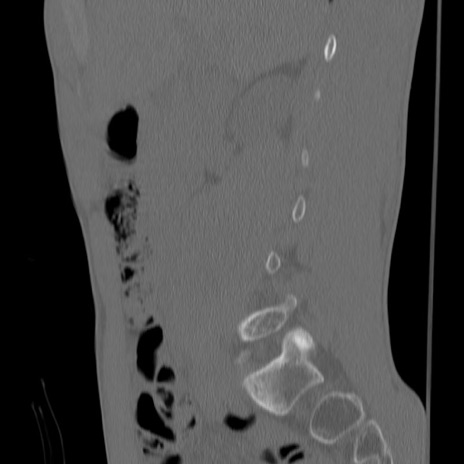

症例3 腰椎CT(矢状断像)

【症例】30歳代男性

【主訴】腰痛

【現病歴】本日旅行先で観光中に、友人と衝突し転倒し受傷。

【身体所見】麻痺なし、右下腿内側前面外側、左下腿内側に知覚鈍麻・しびれ

異常所見と診断は?

腰椎CT